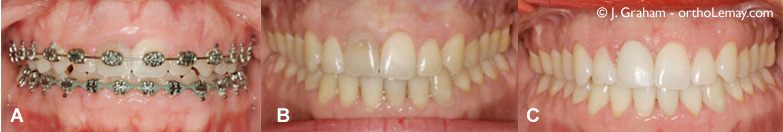

(A) Dentition pendant le traitement, (B) à la fin du traitement et (C) après que la gencive ait été taillée au laser pour lui donner un meilleur contour et qu’une facette ait été faite par le dentiste sur la centrale supérieure droite.

Dentition et occlusion finales